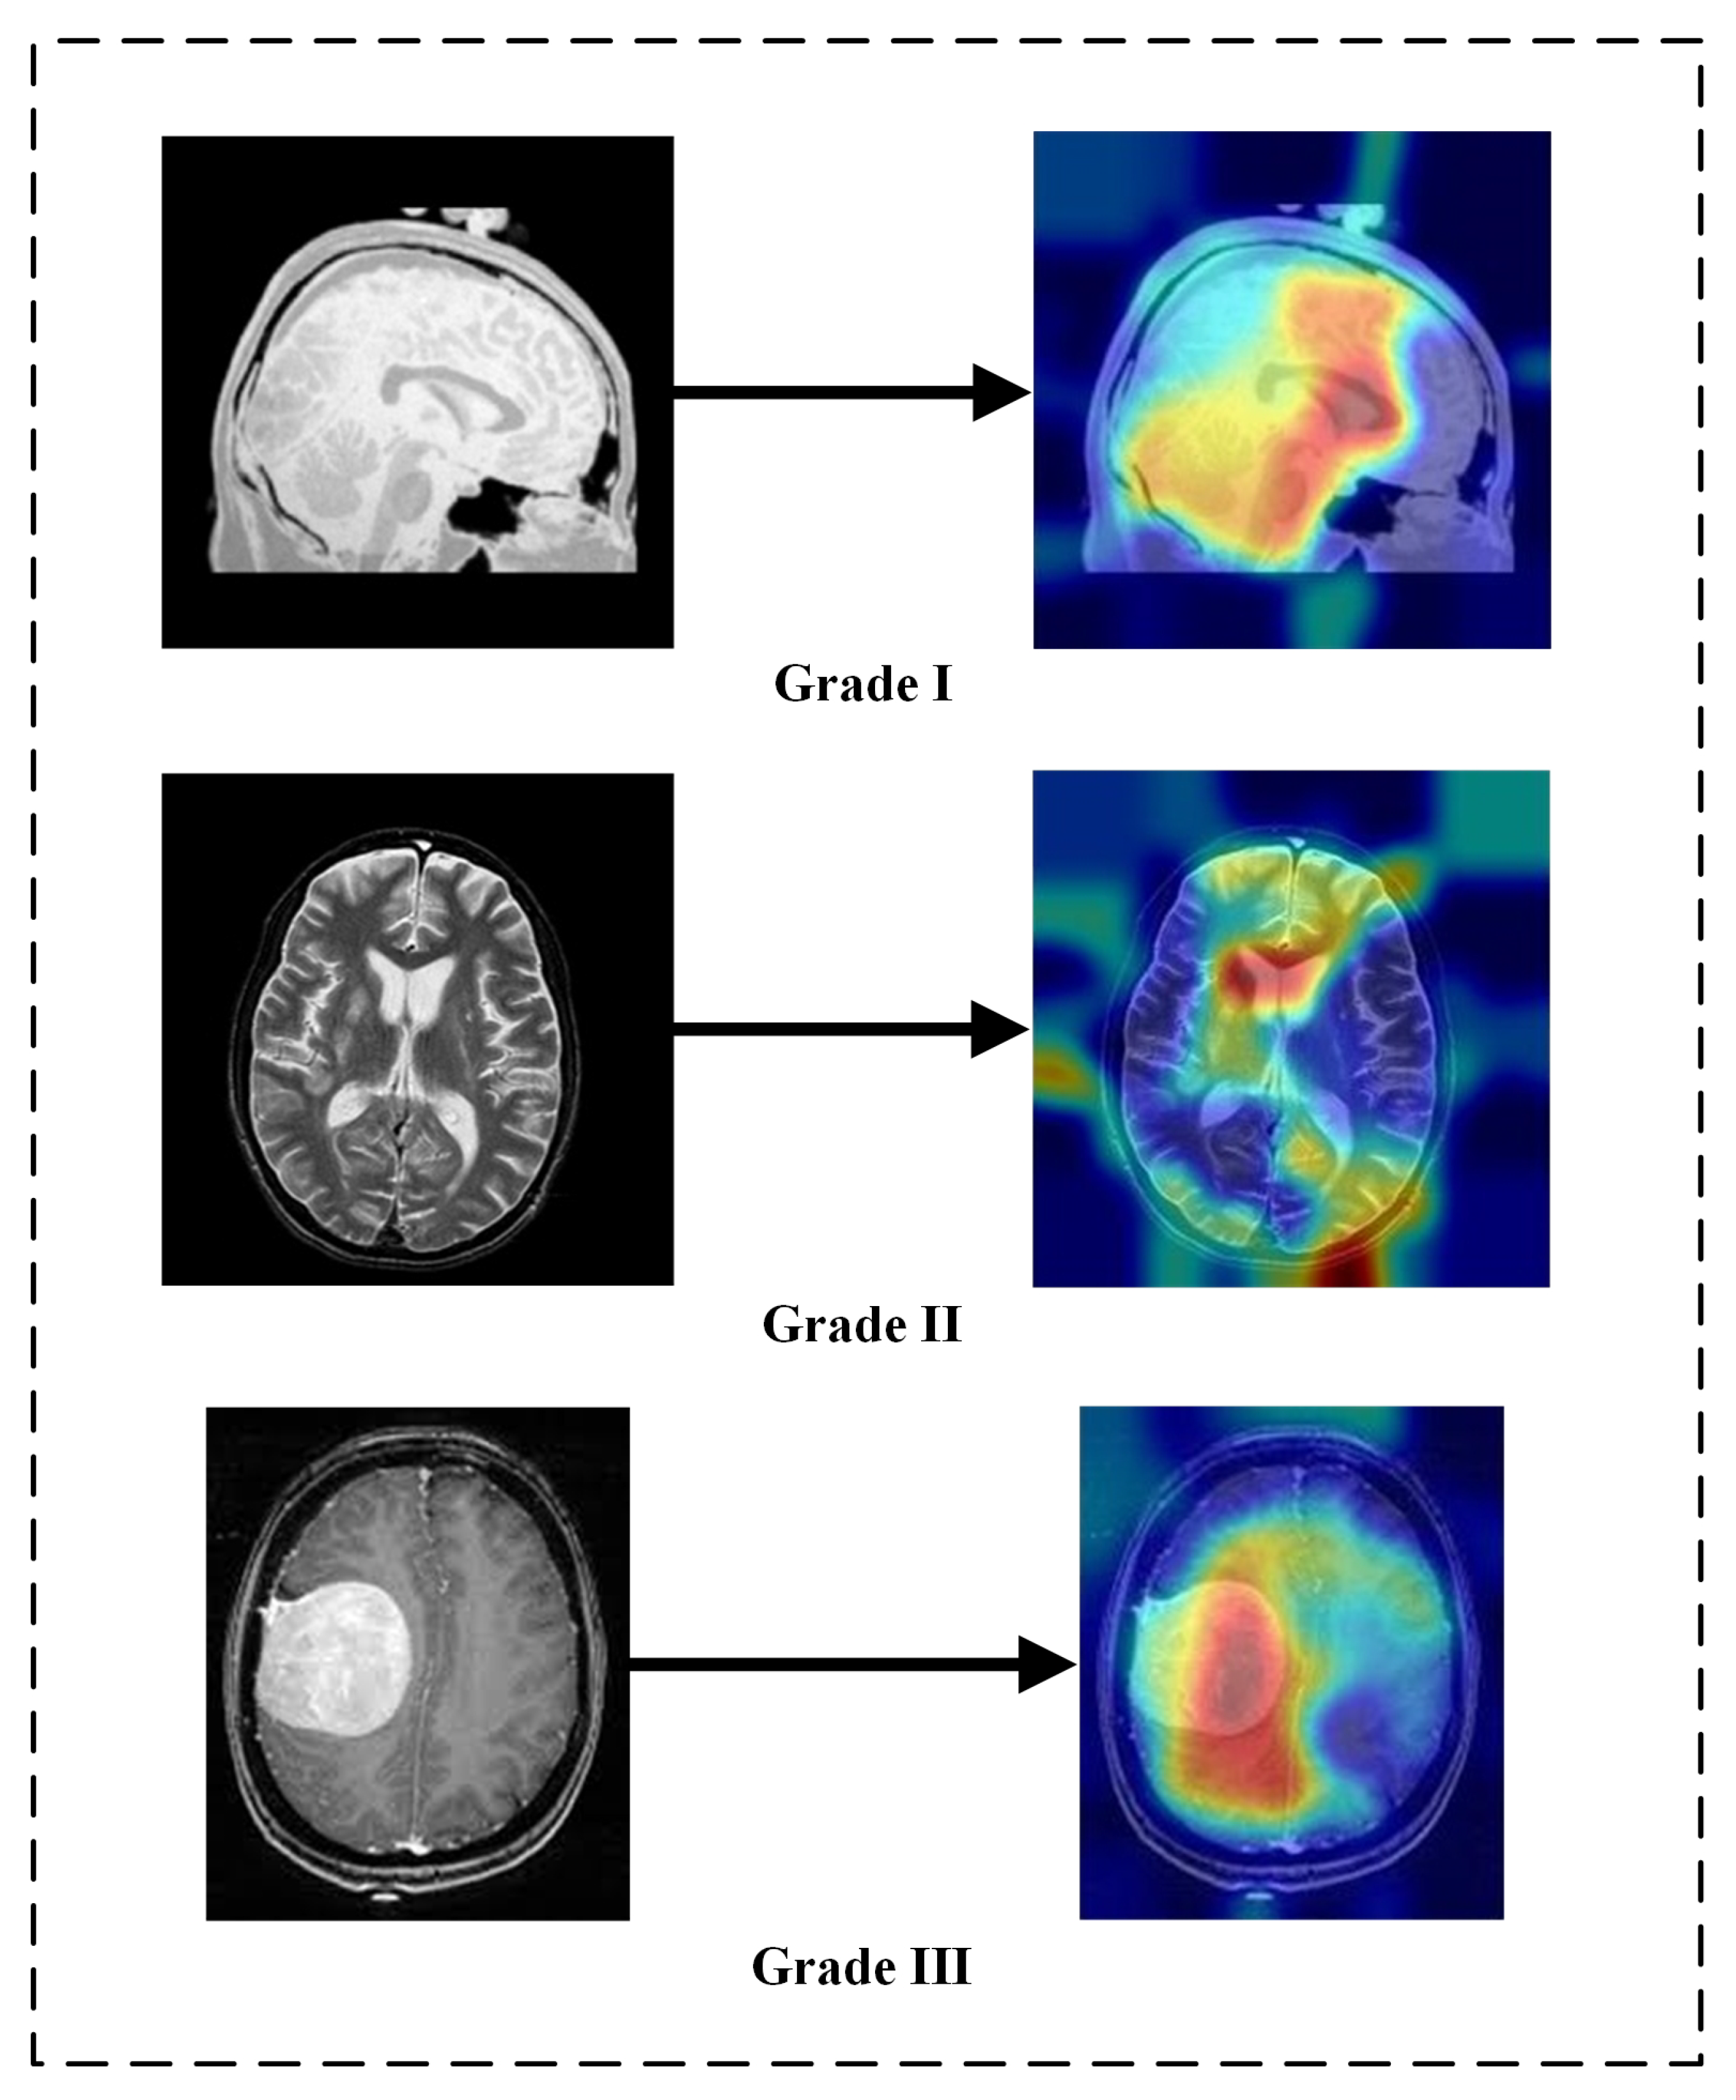

5.3. Explainability of the Results

- Selvaraju, R.R.; Cogswell, M.; Das, A.; Vedantam, R.; Parikh, D.; Batra, D. Grad-CAM: Visual Explanations from Deep Networks via Gradient-Based Localization. Int. J. Comput. Vis. 2019, 128, 336–359. [Google Scholar] [CrossRef]